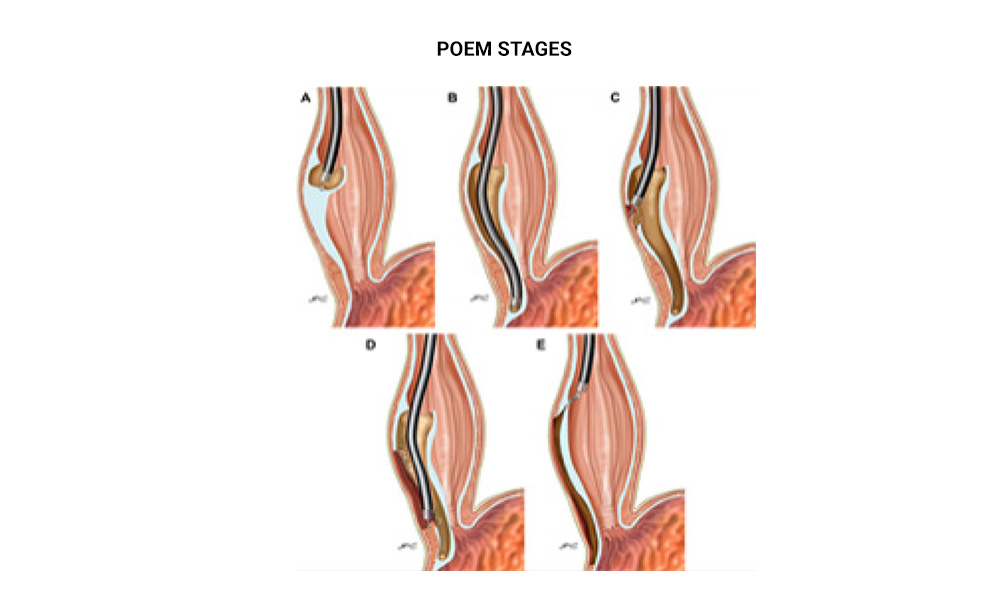

Endoscopic Myotomy For Esophageal Achalasia

Peroral endoscopic myotomy (POEM) for esophageal achalasia has started being performed in Greece in the last two years, exclusively at Metropolitan Hospital, with successful results. The procedure is performed from the mouth with the help of an endoscope, at the Hospital's Endoscopy Department. A special lancet is fitted to the endoscope and with precise movements, it cuts the contracted circular muscle fibers in the lower third of the esophagus which are responsible for causing achalasia.

Disease

Achalasia is the most common benign primary motor disorder of the esophagus, marked by progressively deteriorating dysphagia, regurgitation of undigested food trapped in the dilated esophagus, heartburn and pain, as well as progressive weight loss in advanced stages. These individuals also run the risk of developing aspiration pneumonia from food trapped in the esophagus for days, or even carcinomatous change.

Treatment

Conventional treatment methods include: endoscopic balloon dilation (but with temporary results, high failure rates and frequent revision procedures) and Heller myotomy, which is performed in very severe cases, has high failure rates and is accompanied by an antireflux procedure. The revolutionary peroral endoscopic myotomy (POEM) is the most contemporary, minimally invasive technique for radical treatment of all types of esophageal achalasia.

Conclusions:

Peroral endoscopic myotomy (POEM) may be performed safely and successfully, even on older or gravely ill patients. After POEM, patients do not have any abdominal incisions, are not in pain and may move around freely. They may start receiving liquid food and be discharged on the first postoperative day. POEM assists patients in getting rid of the daily nightmare associated with their eating – which has been going on for decades in some patients – and lets them enjoy better quality of life.